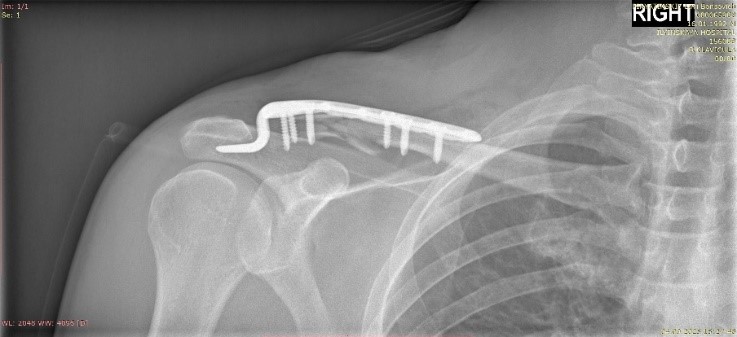

Операция выполнена на следующий день. Выбрана самая стабильная фиксация: крючкообразная пластина для акромиального конца ключицы позволяет восстановить длину и форму самой ключицы, а также убрать нагрузку со связок акромиально-ключичного сочленения, способствовать их сращению заведением крюка под акромиальный отросток лопатки, то есть перенеся в эту точку напряжение с винтов пластины.

Такая пластина обязательна к удалению в перспективе ближайшего полугодия.